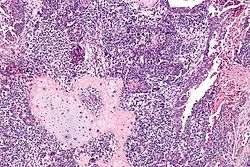

Micrograph of a carcinosarcoma. H&E stain. | |